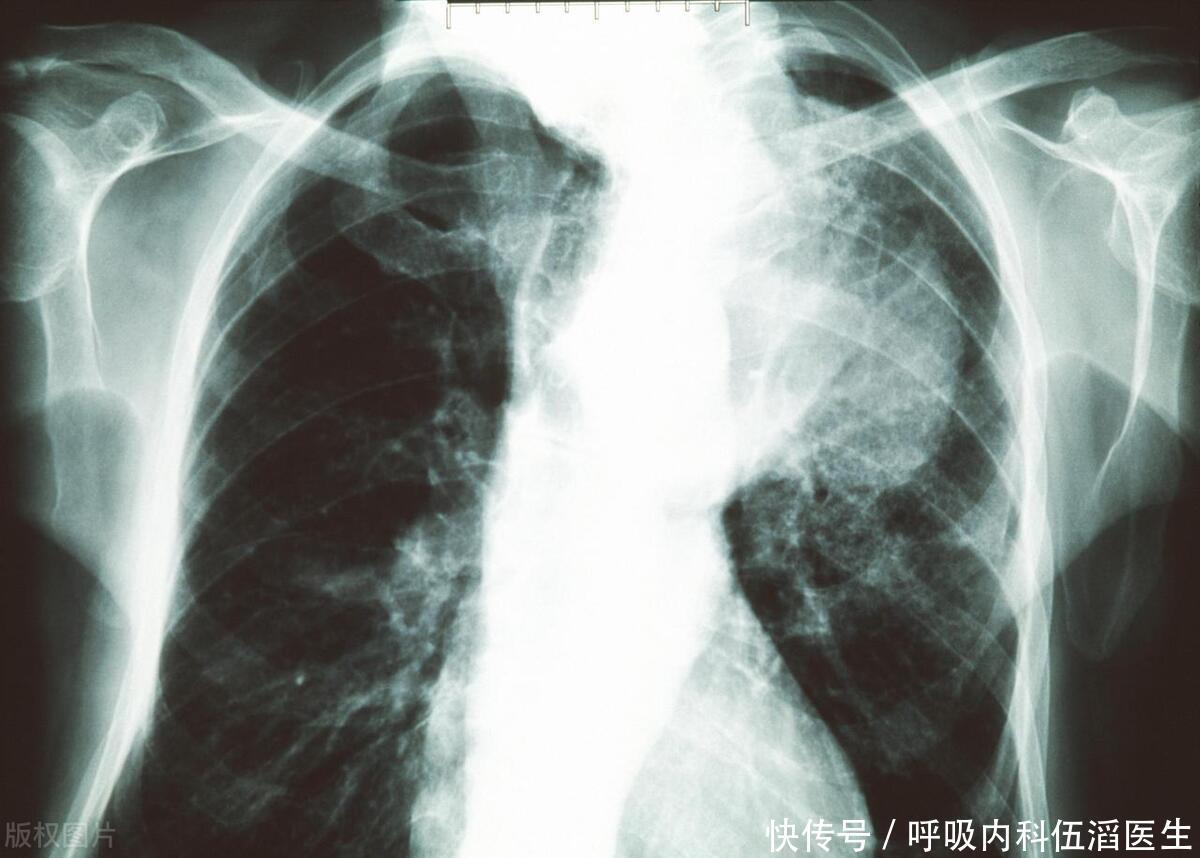

肺癌,作为全球最为常见的癌症之一,其高死亡率备受关注。其严峻形势迫切需要引起社会各界的高度重视和关注。肺癌往往在早期无明显症状,导致晚期诊断增加了治疗的挑战和风险。这强调了早期筛查的必要性,以便及早发现和治疗该疾病。然而,身体往往会通过各种迹象向我们发出健康警报,其中一些迹象甚至可能在不太显眼的地方出现,比如双腿。本文将探讨肺癌与双腿出现的三个可能迹象,以及为什么早期筛查对于提高生存率至关重要。

肺癌早期发现关系到治疗成功率和生存率,这一现实不容小觑,应引起社会广泛关注和高度重视。早期肺癌通常可以通过手术完全切除,而晚期肺癌的治疗选择则更加有限,通常涉及化疗、放疗或靶向治疗等方法。

早期筛查采用低剂量计算机断层扫描(LDCT),这种专为尽早发现肺癌而设计的影像学检查备受肯定,其精准度和有效性在专业领域获得了广泛认可。据已有证据表明,定期进行低剂量计算机断层扫描(LDCT)筛查已被证实对于长期吸烟等高风险人群可显著降低肺癌死亡率。